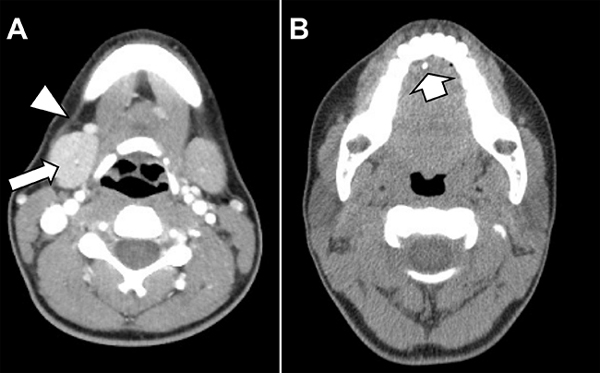

Cortes axiales de TC a la altura del piso de la boca. Paciente que consultó por dolor e hinchazón en región submandibular que se exacerba con la salivación. En el corte inferior de la adquisición post- contraste endovenoso (A) se señala el realce asimétrico de la glándula submandibular derecha (flecha larga) respecto a su contralateral. Existe también un ligero engrosamiento de la fascia cervical superficial adyacente (cabeza de flecha). En el corte superior de la adquisición pre-contraste endovenoso (B) se observó la existencia de un lito en el sector distal del conducto submandibular, a nivel de la carúncula salivar (flecha corta). Dichos hallazgos se atribuyen a sialoadenitis aguda.